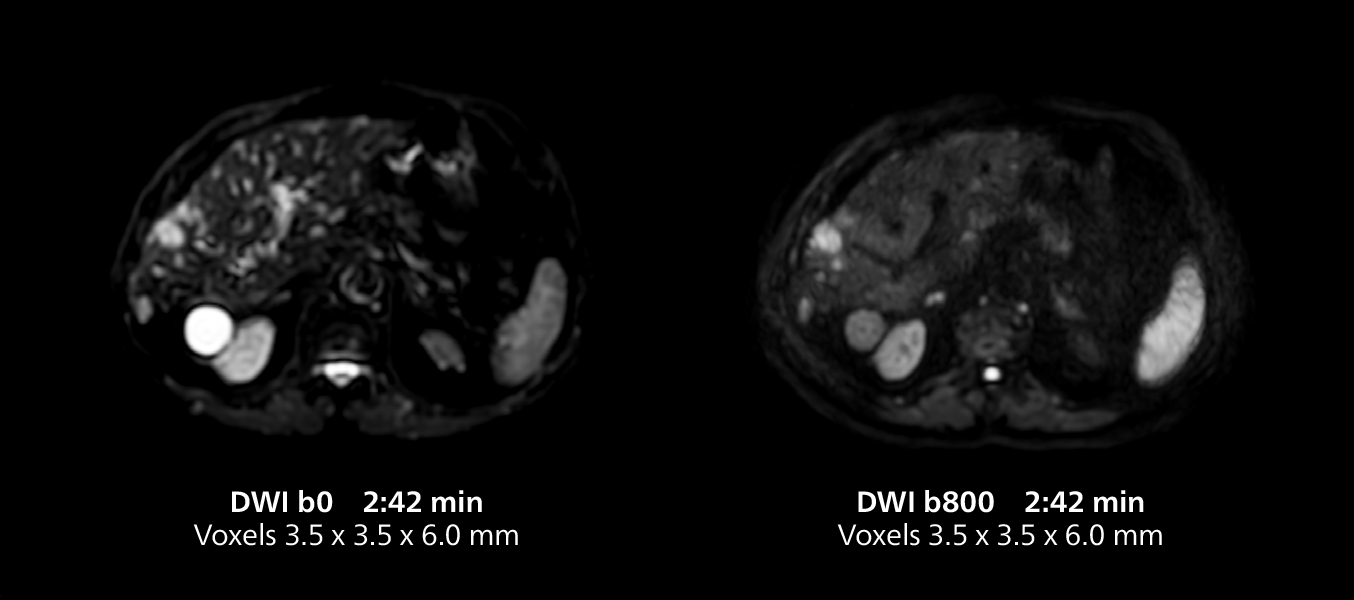

Liver imaging using MR 5300

This case includes 3D free breathing and 4D dynamic free breathing MRI of a metastasized liver. A high quality fatsat sequence with good resolution is obtained in 1:36 minutes with T2-weighted MultiVane XD.